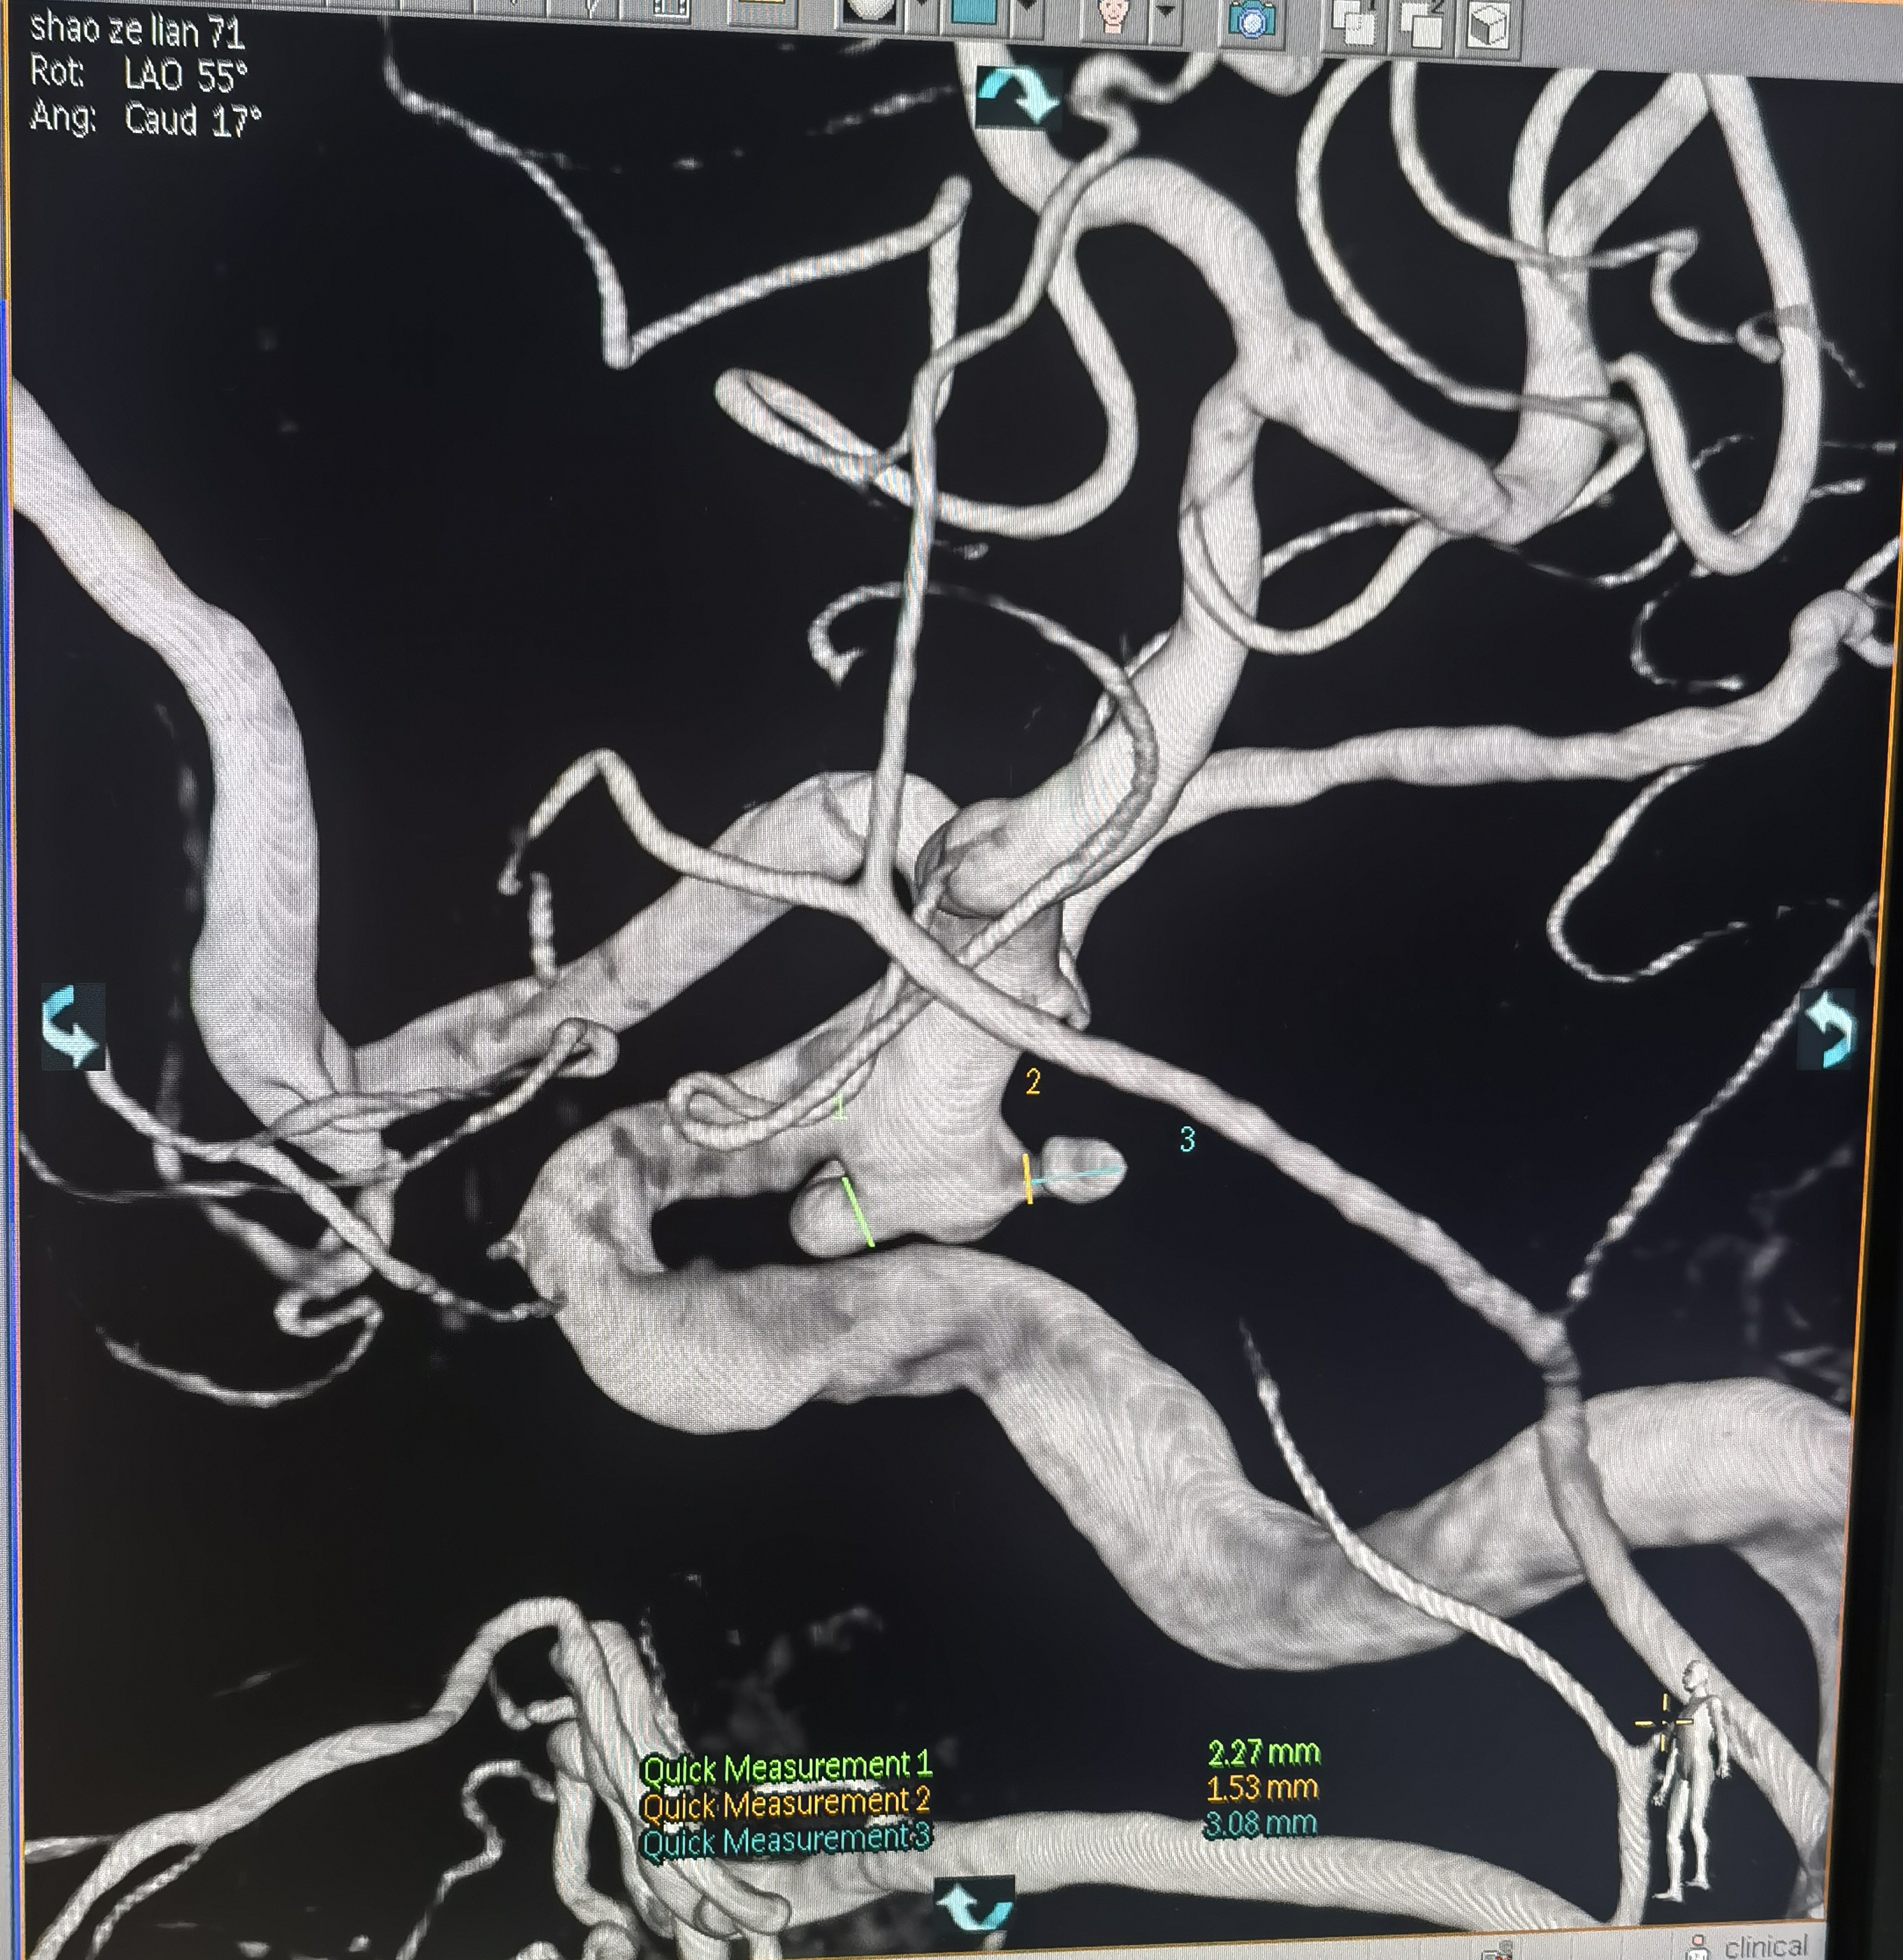

你的浏览器不支持video标签. 入院CT 血管迂曲你的浏览器不支持video标签. RCCA正位,胚胎型大脑后动脉,右侧大脑前动脉纤细。你的浏览器不支持video标签. RCCA3D造影你的浏览器不支持video标签. 右侧3D 右侧后交通动脉瘤形状亦不规则,拟二期治疗。你的浏览器不支持video标签. LCCA正位,胚胎型大脑后动脉,左侧A1供应双侧大脑前动脉。你的浏览器不支持video标签. LCCA3D造影你的浏览器不支持video标签. 左侧3D你的浏览器不支持video标签. 左椎正位,PICA以远未显影。 左侧后交通动脉瘤形状不规则,见子瘤。 拟支架辅助栓塞左侧后交通动脉瘤。 工作位路图,显示子瘤。 微导管首先超选子瘤填塞弹簧圈后,弹簧圈从子瘤脱出,遂应用支架于颈内动脉交通段释放辅助栓塞。你的浏览器不支持video标签. 术中造影你的浏览器不支持video标签. 术中造影你的浏览器不支持video标签. 术中造影你的浏览器不支持video标签. 释放支架,术中造影。你的浏览器不支持video标签. 术后造影你的浏览器不支持video标签. 术后正位你的浏览器不支持video标签. 术后侧位